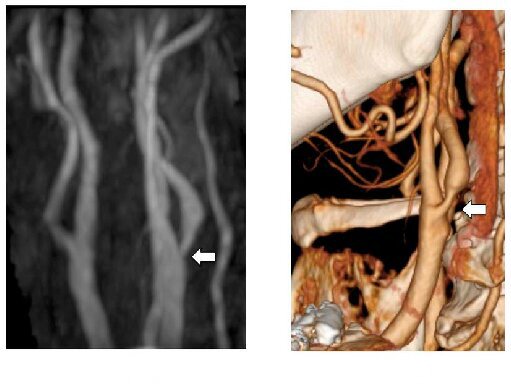

MRA 和 CTA: 頸部動脈嚴重動脈粥狀硬化狹窄